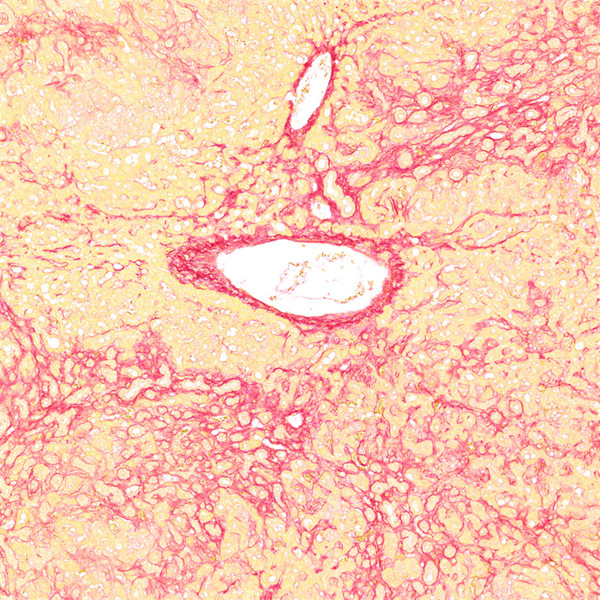

天狼猩红和KWS都是强酸性染料,易与胶原分子中的碱性基团结合,吸附牢固。偏振光镜检查,胶原纤维有正的单轴双折射光的属性,与KWS-天狼猩红结合,可增强双折射,提高分辨率,从而区分两型胶原纤维。未脱钙骨组织切片经天狼猩红染色后,普通光学显微镜下,胶原纤维呈红色或鲜红色,其他呈黄色;在偏振光显微镜下,Ⅰ型胶原纤维呈强橙黄色或亮红色,Ⅲ型胶原纤维呈绿色。

实验结果展示:

<天狼星红-肝>